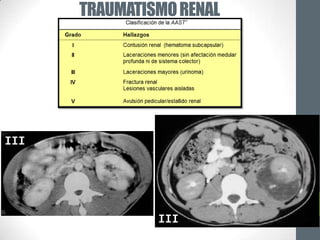

I             II

TRAUMATISMO RENAL

III                       II

III